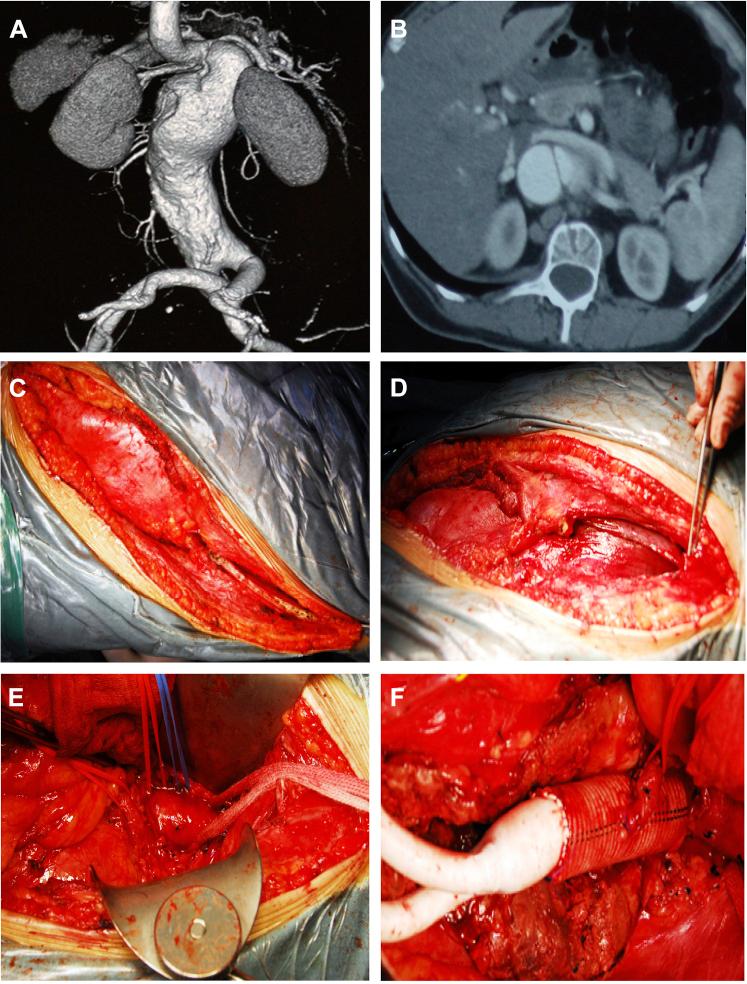

The ninth intercostal thoracoretroperitoneal incision is the most common approach for open repair of suprarenal abdominal aortic aneurysm or abdominal aortic dissection, which necessitates incision of the pleura and diaphragm and may lead to cardiorespiratory distress postoperatively. We optimized this approach by partially removing the tenth rib, bluntly dissecting the diaphragm from its costal edge, and retracting the diaphragm superiorly. We successfully performed this approach in three patients with pararenal abdominal aortic aneurysm, abdominal aortic dissection, or renal artery aneurysm. Based on our experience, this approach allows easy exposure of the suprarenal aorta and avoids thoracotomy, which would potentially benefit patients' prognosis.

第九肋间胸腹后腹膜切口是开放性修复肾上腺区腹主动脉瘤或腹主动脉夹层最常用的方法,该方法需要切开胸膜和膈肌,术后可能导致心肺功能不全。我们通过部分切除第十肋、从肋缘钝性分离膈肌并向上牵拉膈肌对该方法进行了优化。我们成功地对3例肾旁腹主动脉瘤、腹主动脉夹层或肾动脉动脉瘤患者实施了该方法。根据我们的经验,该方法能够轻松暴露肾上腺区腹主动脉,避免开胸手术,这可能对患者的预后有益。